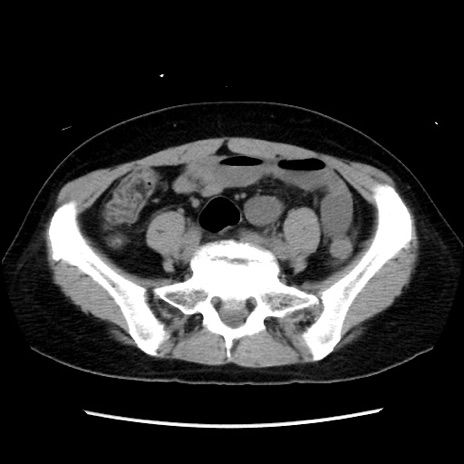

矢状断像